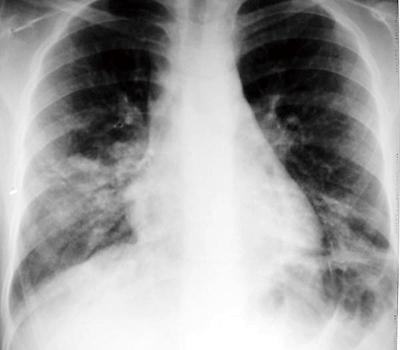

マイコプラズマ菌に感染した肺

A 子どものせきが長引いたり喘鳴があったりしてマイコプラズマ肺炎が疑われる場合は、胸部のレントゲン写真を撮り、血液検査で炎症度や抗体を調べ、医師の臨床的印象に基づいて診断します。マイコプラズマ菌の遺伝子を検出するPCR法を使った検査や、鼻からの分泌物や痰からマイコプラズマ菌を分離する検査もあります。